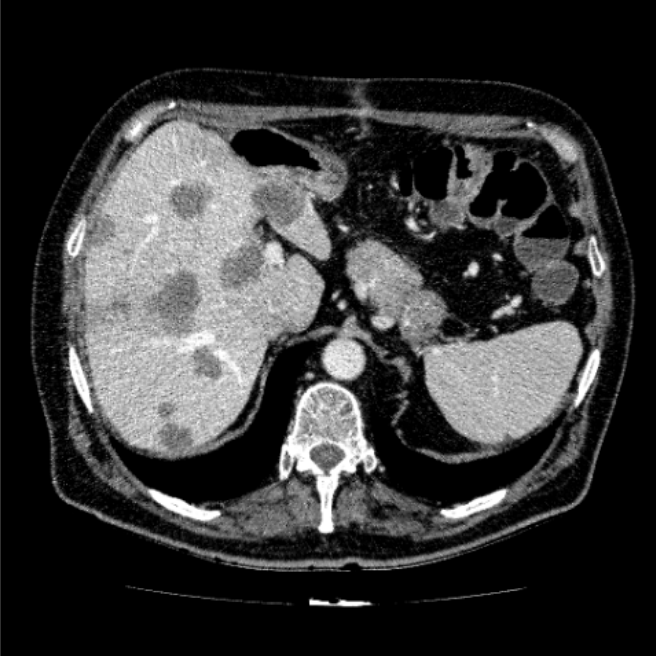

The liver tumor segmentation benchmark (lits)Patrick Bilic, Patrick Christ, Hongwei Bran Li, Eugene Vorontsov, Avi Ben-Cohen, Georgios Kaissis, Adi Szeskin, Colin Jacobs, Gabriel Efrain Humpire Mamani, Gabriel Chartrand, and othersMedical Image Analysis[ bibtex | html | abstract ]@article{bilic2023liver, title = {The liver tumor segmentation benchmark (lits)}, author = {Bilic, Patrick and Christ, Patrick and Li, Hongwei Bran and Vorontsov, Eugene and Ben-Cohen, Avi and Kaissis, Georgios and Szeskin, Adi and Jacobs, Colin and Mamani, Gabriel Efrain Humpire and Chartrand, Gabriel and others}, journal = {Medical Image Analysis}, volume = {84}, pages = {102680}, year = {2023}, publisher = {Elsevier}, abbr = {bilic2023liver.png}, html = {https://www.sciencedirect.com/science/article/pii/S1361841522003085} }In this work, we report the set-up and results of the Liver Tumor Segmentation Benchmark (LITS) organized in conjunction with the IEEE International Symposium on Biomedical Imaging (ISBI) 2016 and International Conference On Medical Image Computing Computer Assisted Intervention (MICCAI) 2017. Twenty four valid state-of-the-art liver and liver tumor segmentation algorithms were applied to a set of 131 computed tomography (CT) volumes with different types of tumor contrast levels (hyper-/hypo-intense), abnormalities in tissues (metastasectomie) size and varying amount of lesions. The submitted algorithms have been tested on 70 undisclosed volumes. The dataset is created in collaboration with seven hospitals and research institutions and manually reviewed by independent three radiologists. We found that not a single algorithm performed best for liver and tumors. The best liver segmentation algorithm achieved a Dice score of 0.96(MICCAI) whereas for tumor segmentation the best algorithm evaluated at 0.67(ISBI) and 0.70(MICCAI). The LITS image data and manual annotations continue to be publicly available through an online evaluation system as an ongoing benchmarking resource.

Automatic liver and tumor segmentation of CT and MRI volumes using cascaded fully convolutional neural networksPatrick Ferdinand Christ, Florian Ettlinger, Felix Grün, Mohamed Ezzeldin A Elshaera, Jana Lipkova, Sebastian Schlecht, Freba Ahmaddy, Sunil Tatavarty, Marc Bickel, Patrick Bilic, and othersarXiv preprint arXiv:1702.05970[ bibtex | html | abstract ]@article{christ2017automatic, title = {Automatic liver and tumor segmentation of CT and MRI volumes using cascaded fully convolutional neural networks}, author = {Christ, Patrick Ferdinand and Ettlinger, Florian and Gr{\"u}n, Felix and Elshaera, Mohamed Ezzeldin A and Lipkova, Jana and Schlecht, Sebastian and Ahmaddy, Freba and Tatavarty, Sunil and Bickel, Marc and Bilic, Patrick and others}, journal = {arXiv preprint arXiv:1702.05970}, year = {2017}, abbr = {christ2017automatic.png}, html = {https://arxiv.org/abs/1702.05970} }Automatic segmentation of the liver and hepatic lesions is an important step towards deriving quantitative biomarkers for accurate clinical diagnosis and computer-aided decision support systems. This paper presents a method to automatically segment liver and lesions in CT and MRI abdomen images using cascaded fully convolutional neural networks (CFCNs) enabling the segmentation of a large-scale medical trial or quantitative image analysis. We train and cascade two FCNs for a combined segmentation of the liver and its lesions. In the first step, we train a FCN to segment the liver as ROI input for a second FCN. The second FCN solely segments lesions within the predicted liver ROIs of step 1. CFCN models were trained on an abdominal CT dataset comprising 100 hepatic tumor volumes. Validations on further datasets show that CFCN-based semantic liver and lesion segmentation achieves Dice scores over 94% for liver with computation times below 100s per volume. We further experimentally demonstrate the robustness of the proposed method on an 38 MRI liver tumor volumes and the public 3DIRCAD dataset.

Automated unsupervised segmentation of liver lesions in ct scans via cahn-hilliard phase separationJana Lipková, Markus Rempfler, Patrick Christ, John Lowengrub, and Bjoern H MenzearXiv preprint arXiv:1704.02348[ bibtex | html | abstract ]@article{lipkova2017automated, title = {Automated unsupervised segmentation of liver lesions in ct scans via cahn-hilliard phase separation}, author = {Lipkov{\'a}, Jana and Rempfler, Markus and Christ, Patrick and Lowengrub, John and Menze, Bjoern H}, journal = {arXiv preprint arXiv:1704.02348}, year = {2017}, abbr = {lipkova2017automated.png}, html = {https://arxiv.org/pdf/1704.02348.pdf} }The segmentation of liver lesions is crucial for detection, di- agnosis and monitoring progression of liver cancer. However, design of accurate automated methods remains challenging due to high noise in CT scans, low contrast between liver and lesions, as well as large lesion variability. We propose a 3D automatic, unsupervised method for liver le- sions segmentation using a phase separation approach. It is assumed that liver is a mixture of two phases: healthy liver and lesions, represented by different image intensities polluted by noise. The Cahn-Hilliard equation is used to remove the noise and separate the mixture into two distinct phases with well-defined interfaces. This simplifies the lesion detection and segmentation task drastically and enables to segment liver lesions by thresholding the Cahn-Hilliard solution. The method was tested on 3Dircadb and LITS dataset.